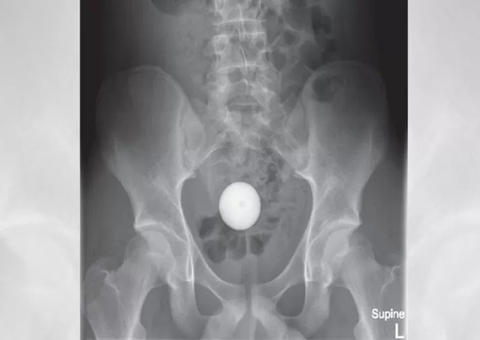

A chave foi arremessada em sua direção e, quando tentou agarrar no ar, acabou puxando o objeto em direção ao rosto e a ponta afiada acabou perfurando a pele, penetrando na cavidade nasal.

A mulher contou que não sentiu dor no momento, por conta da adrenalina, no entanto, quando olhou o rosto no reflexo do carro, viu a chave cravada.